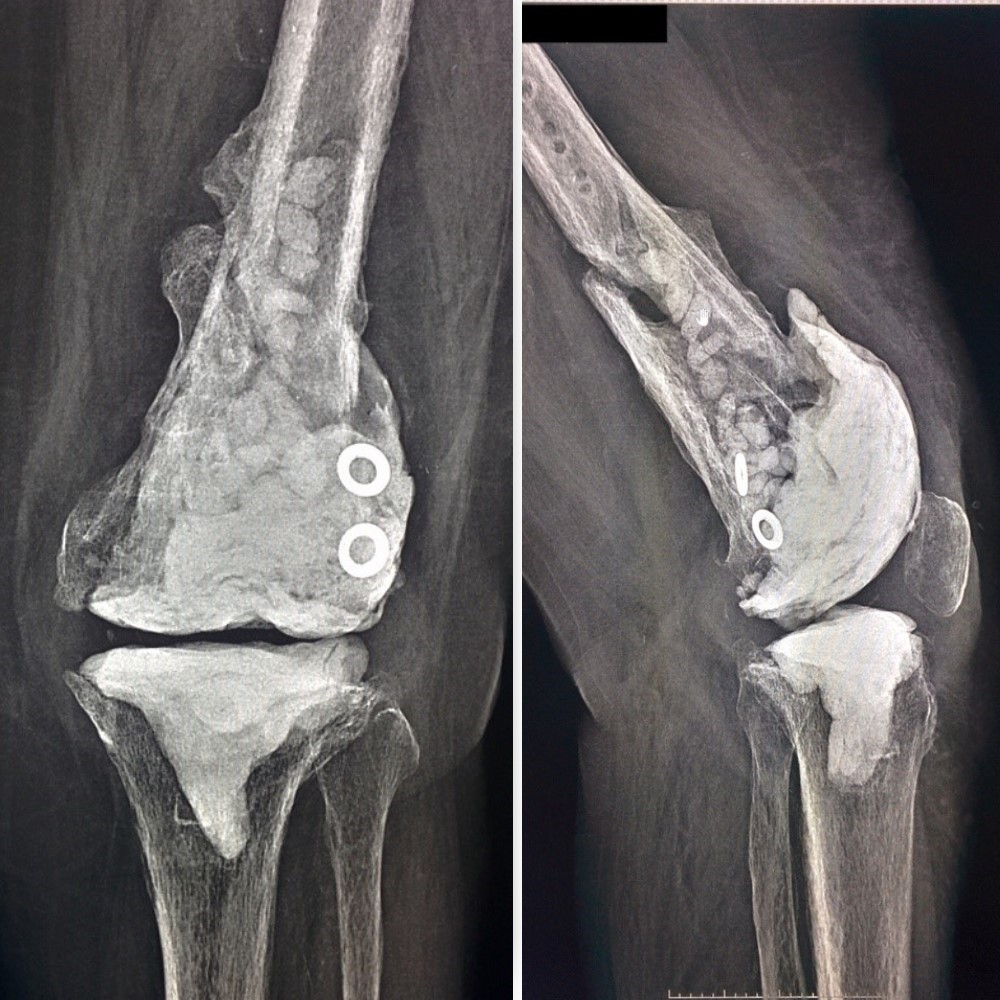

РКТ до ревизии

Сегодняшний день.

ps. извинение за разнобой по другому не вышло.